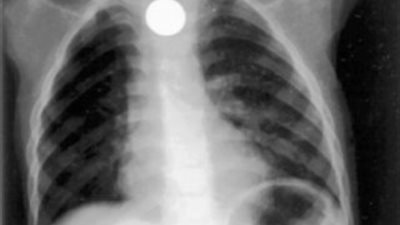

وأوضح مصدر لـ القاهرة 24، أنه تم نقل الطفلة حديثة الولادة إلى حضانة مستشفى الباجور العام، لاتخاذ الإجراءات الطبية اللازمة وبالكشف عليها وجد أن حالتها العامة جيدة ويتم متابعتها عن طريق أطباء الأطفال والتمريض المتخصص.